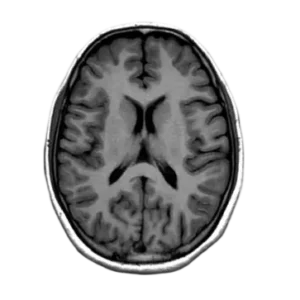

Comprehensive training in diagnostic cerebral angiography techniques and interpretation.